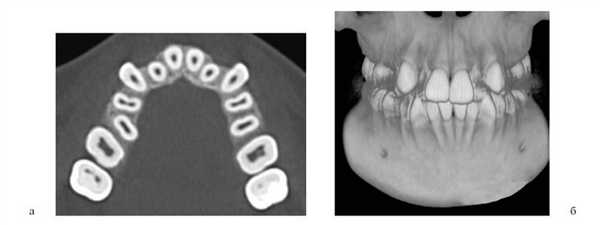

Адаптируясь к уменьшенному размеру челюстей, корни или зачатки зубов размещаются в альвеолярном отростке более компактно. Если зачатки резцов на верхней челюсти из-за недостатка пространства не могут располагаться по периметру альвеолярного отростка, они смещаются небно. При максимально компактном расположении уже постоянный центральный резец смещен небно от одноименного временного (рис. 1). Рисунок 1. Положение коронок зачатков постоянных центральных резцов за корнями одноименных временных (пациент И.Е.).

Положение корней боковых резцов за корнями центральных также отражает существенный недостаток пространства во фронтальном отделе (рис. 2), Рисунок 2. Положение корней боковых резцов за корнями центральных. а, б — пациент В.В.; в, г — пациент Х.А. при этом они равномерно располагаются в альвеолярном отростке.

Коронки боковых резцов при значительной инклинации могут камуфлировать небную позицию их корней. Язычное расположение резцов на нижней челюсти (НЧ) наблюдается редко, так как уменьшение ее размеров сочетается с небольшой шириной альвеолярного отростка; чаще корни резцов располагаются плотно друг к другу, как бы исходя своими верхушками из одной точки и расходясь по мере увеличения их мезиодистального диаметра (рис. 3). Рисунок 3. Плотное расположение корней резцов (пациент М.Д.). Такое проявление максимально компактного расположения резцов НЧ описано в литературе как «симптом букета» [1].